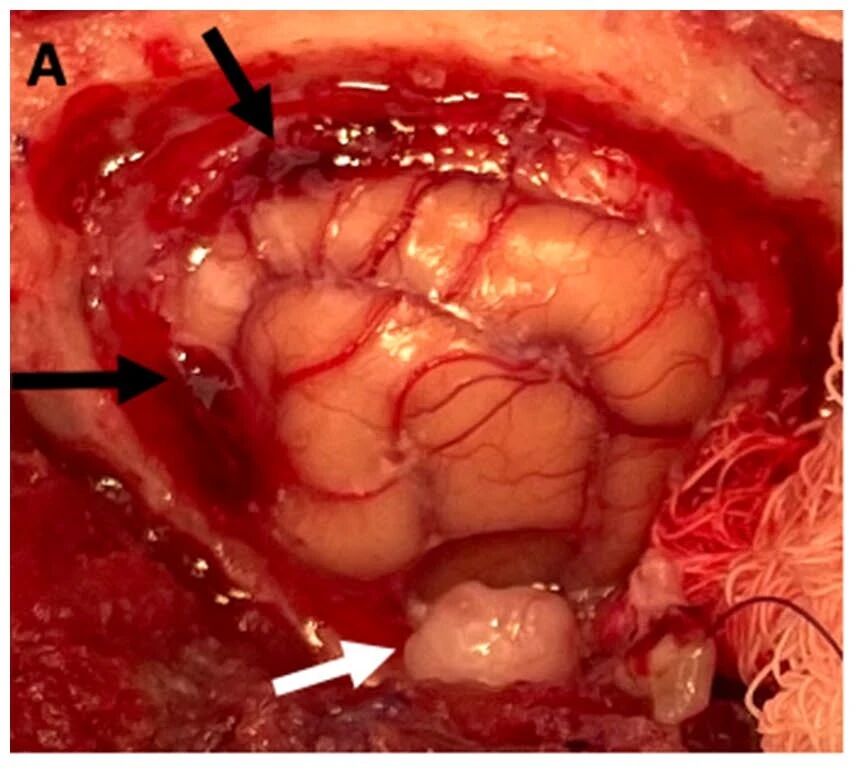

行左侧颅顶颅骨切除术,范围自囟门及矢状缝延伸至颧弓水平(下图)。整个手术视野内,脑膜增厚呈不透明状,呈黄褐色变,背侧及前侧可见出血灶。行局部硬脑膜切除术后,发现暴露脑表面弥漫分布着淡褐色硬膜下渗出物。颧弓水平外侧颞回尾侧可见淡黄色圆形1厘米颅外肿块,压迫脑组织,经整体切除。取脑膜及颞部肿块样本送检细胞学、培养及组织病理学分析。于硬膜缺损处植入猪小肠粘膜下层移植物,并采用钛网进行颅骨修复,以三枚1.5×7毫米钛螺钉固定。

↑ 硬脑膜切除后左侧大脑半球,背侧及前侧可见出血性脑膜(黑色箭头)。左颞叶区域的孤立性肿块由白色箭头标示。